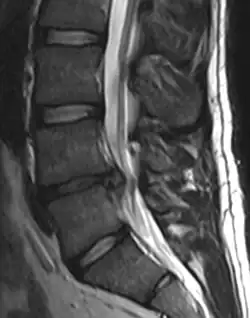

A herniated disc as seen on MRI, one possible cause of low back pain

The straight leg raise test can detect pain originating from a herniated disc. When warranted, imaging such as MRI can provide clear detail about disc related causes of back pain (L4–L5 disc herniation shown).

Imaging is indicated when there are red flags, ongoing neurological symptoms that do not resolve, or ongoing or worsening pain.[5] In particular, early use of imaging (either MRI or CT) is recommended for suspected cancer, infection, or cauda equina syndrome.[5] MRI is slightly better than CT for identifying disc disease; the two technologies are equally useful for diagnosing spinal stenosis.[5] Only a few physical diagnostic tests are helpful.[5] The straight leg raise test is almost always positive in those with disc herniation,[5] and lumbar provocative discography may be useful to identify a specific disc causing pain in those with chronic high levels of low back pain.[47] Therapeutic procedures such as nerve blocks can also be used to determine a specific source of pain.[5] Some evidence supports the use of facet joint injections, transforminal epidural injections and sacroiliac injections as diagnostic tests.[5] Most other physical tests, such as evaluating for scoliosis, muscle weakness or wasting, and impaired reflexes, are of little use.[5]